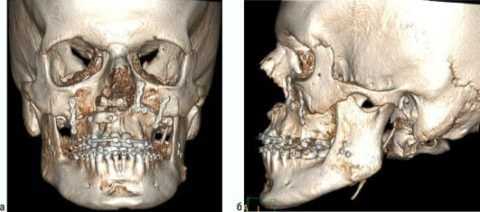

(Слева) Трехмерная реконструкция (вид со стороны язычной поверхности) у этого же пациента позволяет оценить выраженность распространения в нижнюю кортикальную пластинку и дольчатый характер образования.

(Слева) КТ в костном окне, аксиальная проекция. Типичная хондросаркома левого височно-нижнечелюстного суаава. Мыщелок нижней челюсти склерозирован и имеет неправильную форму, внутри и вокруг сустава рассеянны множественные кальцификаты. И хотя в данном случае достаточно сложно дифференцировать заболевание от синовиального хондроматоза, в обоих случаях лечение должно быть хирургическим, а точный диагноз будет установлен после гистологического исследования.

(Справа) Реконструкция в сагиттальной плоскости, этот же пациент. Мыщелок деформирован, а часть кальцификатов находится в мягких тканях вне сустава.